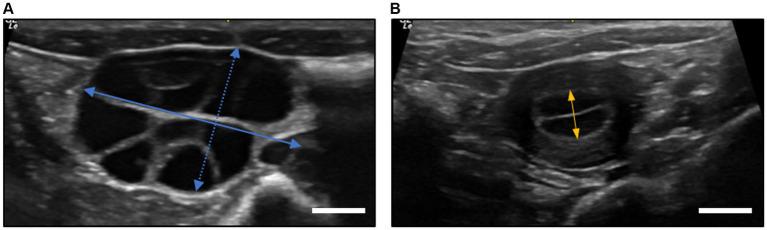

This study involved 23 cynomolgus monkeys divided into two groups-12 superovulated recipients and 11 synchronized recipients. The evaluation criteria included measuring endometrial thickness on the day of embryo transfer and calculating pregnancy and implantation rates to compare outcomes between groups.

The study found no statistically significant differences in endometrial thickness (superovulated: 4.48 ± 1.36 mm, synchronized: 5.15 ± 1.58 mm), pregnancy rates (superovulated: 30.8%, synchronized: 41.7%), and implantation rates (superovulated: 14.3%, synchronized: 21.9%) between the groups ( > 0.05).

研究发现两组之间在子宫内膜厚度(超排卵组:4.48±1.36毫米,同步组:5.15±1.58毫米)、妊娠率(超排卵组:30.8%,同步组:41.7%)和着床率(超排卵组:14.3%,同步组:21.9%)方面均无统计学显著差异(P>0.05)。